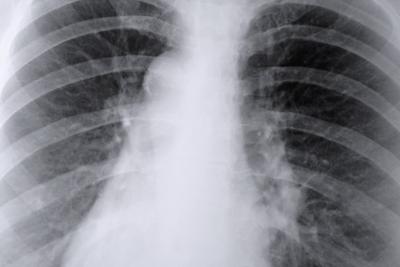

一个与吸烟相关的主要负面健康问题是肺组织的破坏。当你吸烟时,肺组织在多个方面遭到损伤。在某些情况下,伤害是永久性的,甚至危及生命,根据美国癌症协会。

吸烟带来了4000多种化学物质进入你的肺部,其中一些是致癌物质,据戒烟吧jyb8。致癌化学物质损伤肺组织,通过改变正常细胞转化为癌细胞。肺癌是一种致命的疾病。随着时间的推移,吸烟还杀死肺组织,减少肺容量,使患者难以呼吸。

大部分肺组织的损害是一直发生的。例如,包含在香烟烟雾中的致癌化学物质通常需要积累一段时间,然后才会招致终癌变情况发生。招致永久性肺损坏的时间因人而异,在某些程度上取决于天天吸的香烟数量。